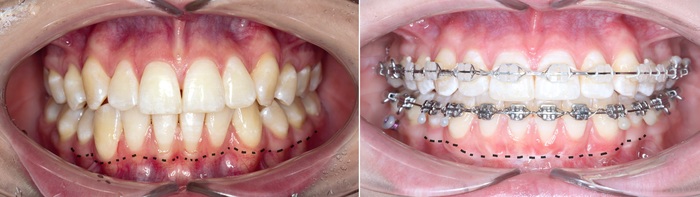

После снятия коронки:

Выкрутили абатмент:

Установлена заглушка, которая закрывает шахту имплантата.

Теперь необходимо выждать около 2-х месяцев для того, чтобы десна восстановилась (Пациентка это время ходила со специальной капой, которая имитирует наличие зуба).

Далее проведена пластика десны, снова два месяца ожиданий и установка временной коронки: